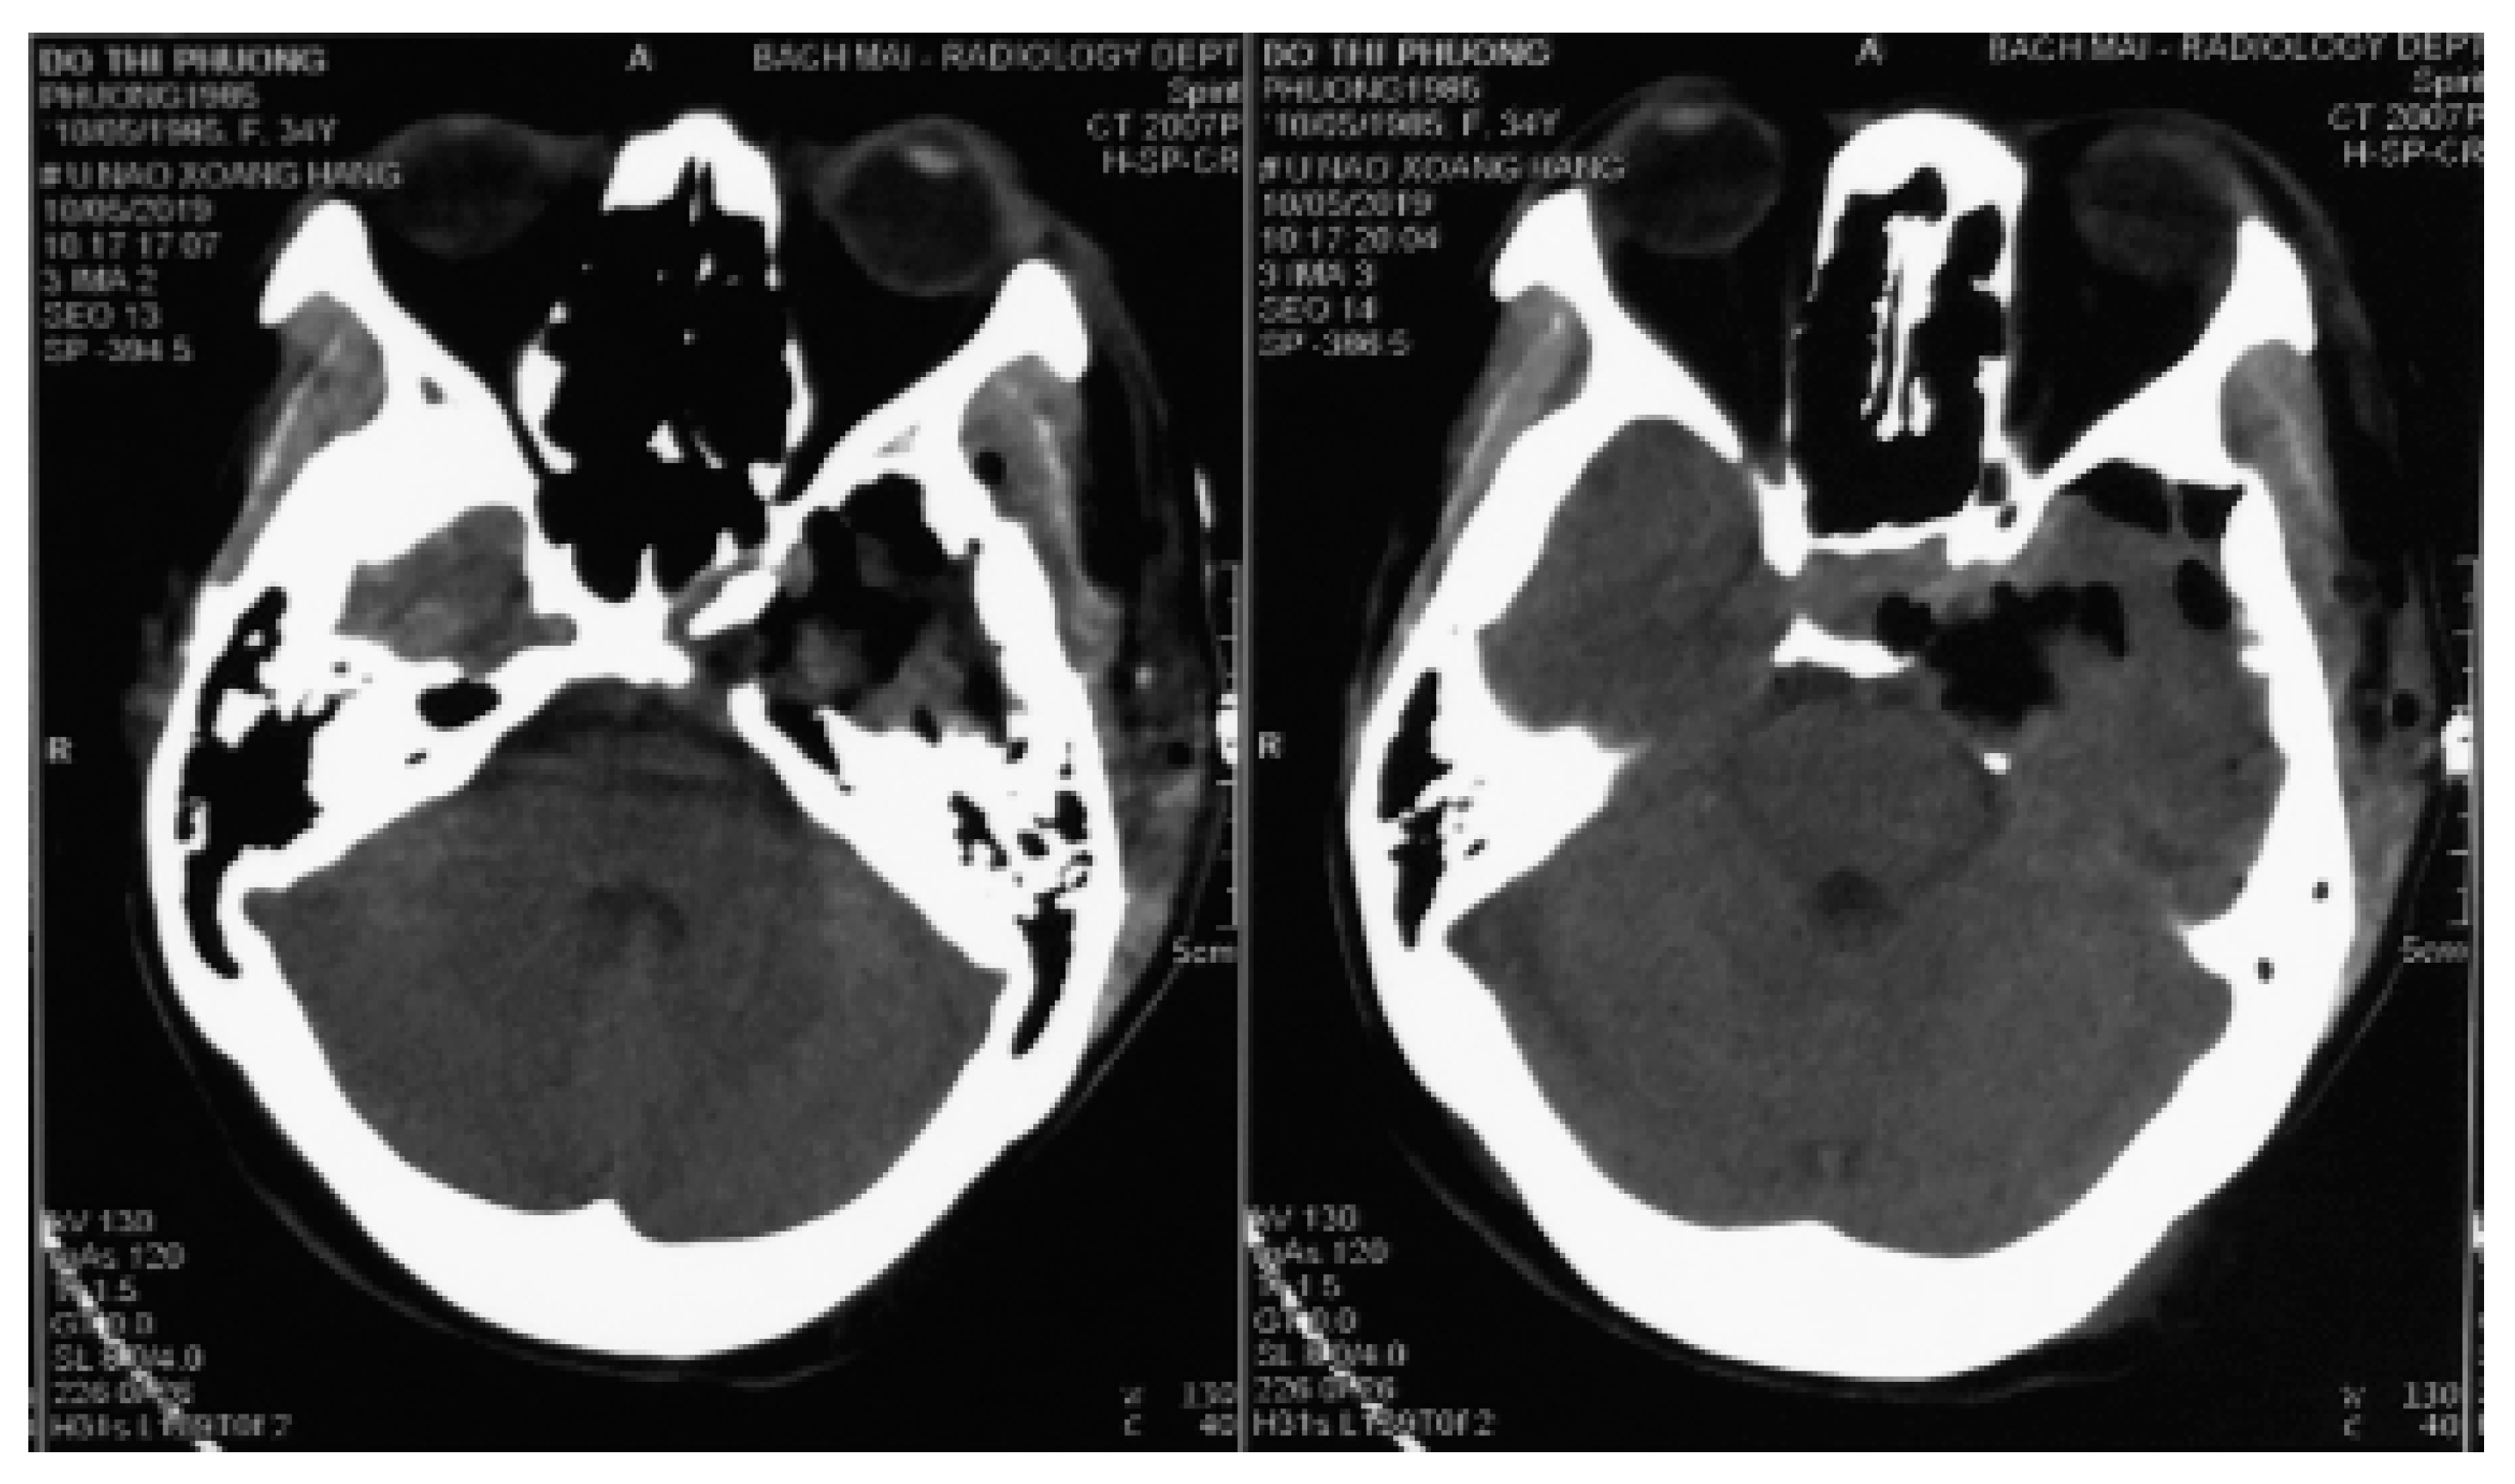

2. Case Presentation